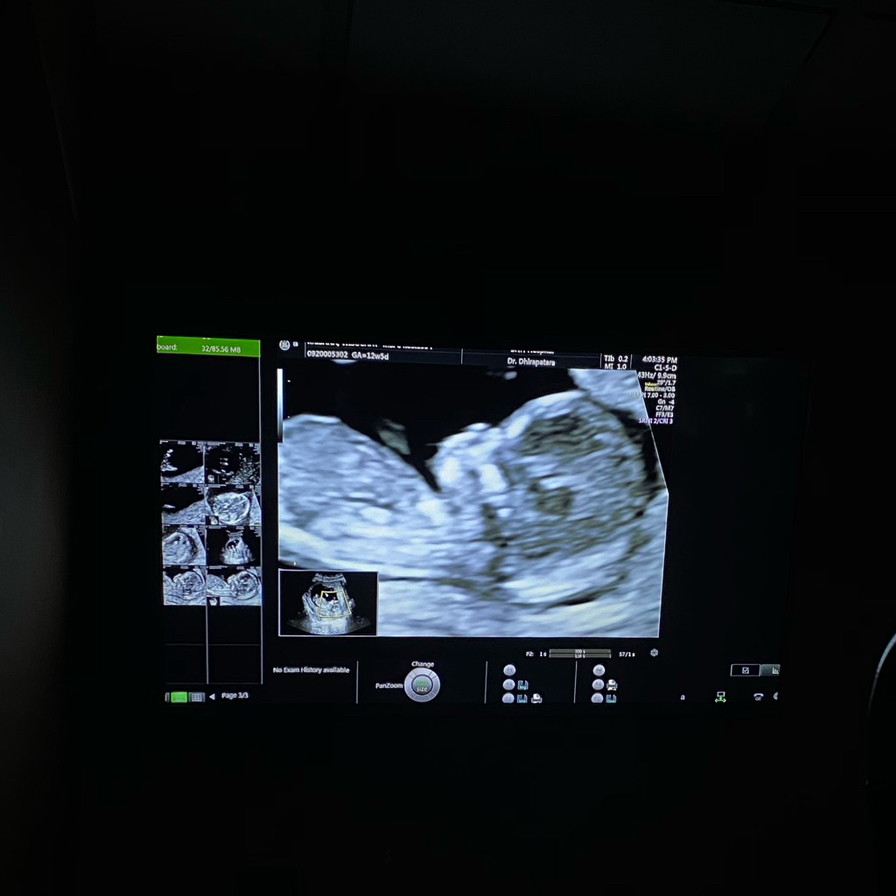

ภาพนี้ตอน12 wค่ะ